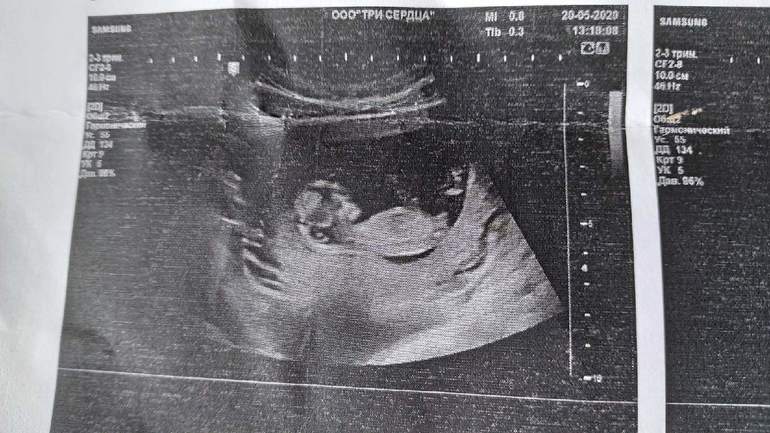

узи, кого видите?

Пол малышаНашла узи, кого видите? На кого похоже?😁

Узист мальчика увидел, я все кручу верчу снимки мне вообще ничего не видно😁Говорят они как то по углу предполагают

На самом первом фото бугорок под углом,похож на мальчишеский...А дальше просто может так сделано фото)Но на таком сроке,если узист не опытный,то могут быть ошибки,конечно.У мальчиков обычно просто более выраженный угол вверх...

Больше похоже на девочку. Хотя небольшой угол отклонения как будто есть, но совсем мало

У мальчиков обычно сильнее задран бугорок. На этом фото похоже на девочку. Недели через 2 будет уже хорошо видно, если пацан